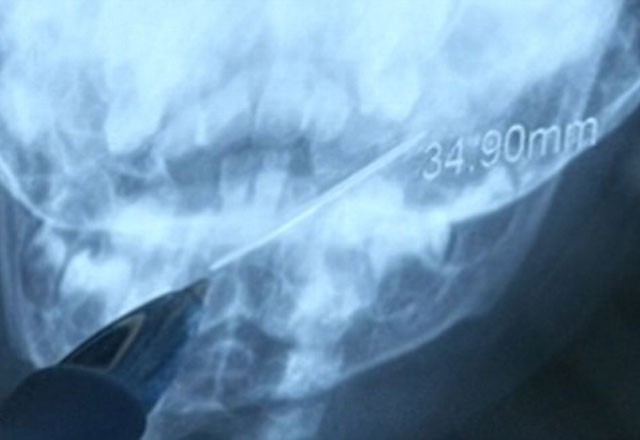

Daily Mail'de yayınlanan habere göre, Çin'de 1 yaşındaki bebek 4 cm'lik iğne yuttu. Xi'an adındaki bebek metali yuttuktan saatler sonra hastaneye yetiştirildi.

Doktorlar iğneyi çıkarmak için ince, esnek, ucunda kamera bulunan boruyu bebeğin boğazına sokarak endoskopi işlemini gerçekleştirdi.

4 cm'lik iğnenin bir ucu bademciklerine değerken diğer ucu gırtlağındaydı. Acilen çıkarılmazsa iç kanamaya veya enfeksiyona neden olabilirdi.